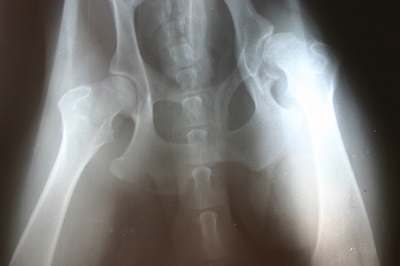

אישה, שעבדה במשך שנים כאחות וכמורה לנהיגה, סבלה מכאבים עזים בגבה וברגליה ומקשיים בהליכה. האישה פנתה לרופא שאיבחן אותה כסובלת מספונדילוליסטזיס – החלקה של חוליה על גבי חוליה אחרת, שיכולה להיות מולדת או ניוונית.

הרופא ניתח את האישה בגבה, בניתוח שכלל השתלת עצם וקיבוע עמוד השדרה. לאחר הניתוח התברר שהשתל לא התאחה, וכי בורג בהתקן הקיבוע נשבר. האישה נותחה שוב לתיקון המצב, אך גם לאחר הניתוח השני התברר כי שני ברגים של התקן הקיבוע נשברו, כך שמצבה לא השתפר.

בתביעתה טענה, כי המנתח סיווג את מחלתה, בטעות, כמולדת ולא כניוונית, והתרשל בכך שביצע בה ניתוח שאינו מתאים לטיפול במצבה. עוד טענה התובעת, כי המנתח ובית החולים הפרו את חובת הגילוי המוטלת עליהם, כשלא ניתן לה הסבר על המחלה האמיתית ממנה היא סובלת.

מומחה מטעם התובעת אישר, כי מחלת האישה היא ניוונית ולא מולדת, וכי השיטה שננקטה בשני הניתוחים היתה שגויה. המומחה אף כינה את הניתוחים "אימפרוביזציה כירורגית רשלנית".

מנגד טען הנתבע, כי הניתוח שביצע מתאים לטיפול בשתי המחלות, וכי שני הטיפולים מקובלים ומובילים לתוצאות דומות. עוד טען, כי על אף השברים בברגים, הניתוח השני כלל לא כשל. לדבריו, זוהי תופעה נפוצה, שאינה מעידה כי השתל לא יתאחה בעתיד.

פגיעה באוטונומיה

השופטת אסתר שטמר קבעה, כי הנתבע אכן שגה באבחנה המדוייקת של מחלת התובעת. עם זאת קבעה, כי הניתוח שבחר הנתבע לבצע היה בדרך אפשרית ומקובלת לטיפול במחלה ממנה התובעת סבלה בפועל, ולכן, אין לראות בבחירת סוג הטיפול כרשלנות מצידו.